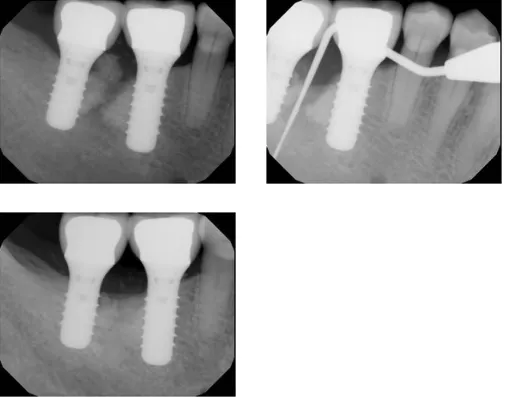

Regenerative Therapy

Before & After